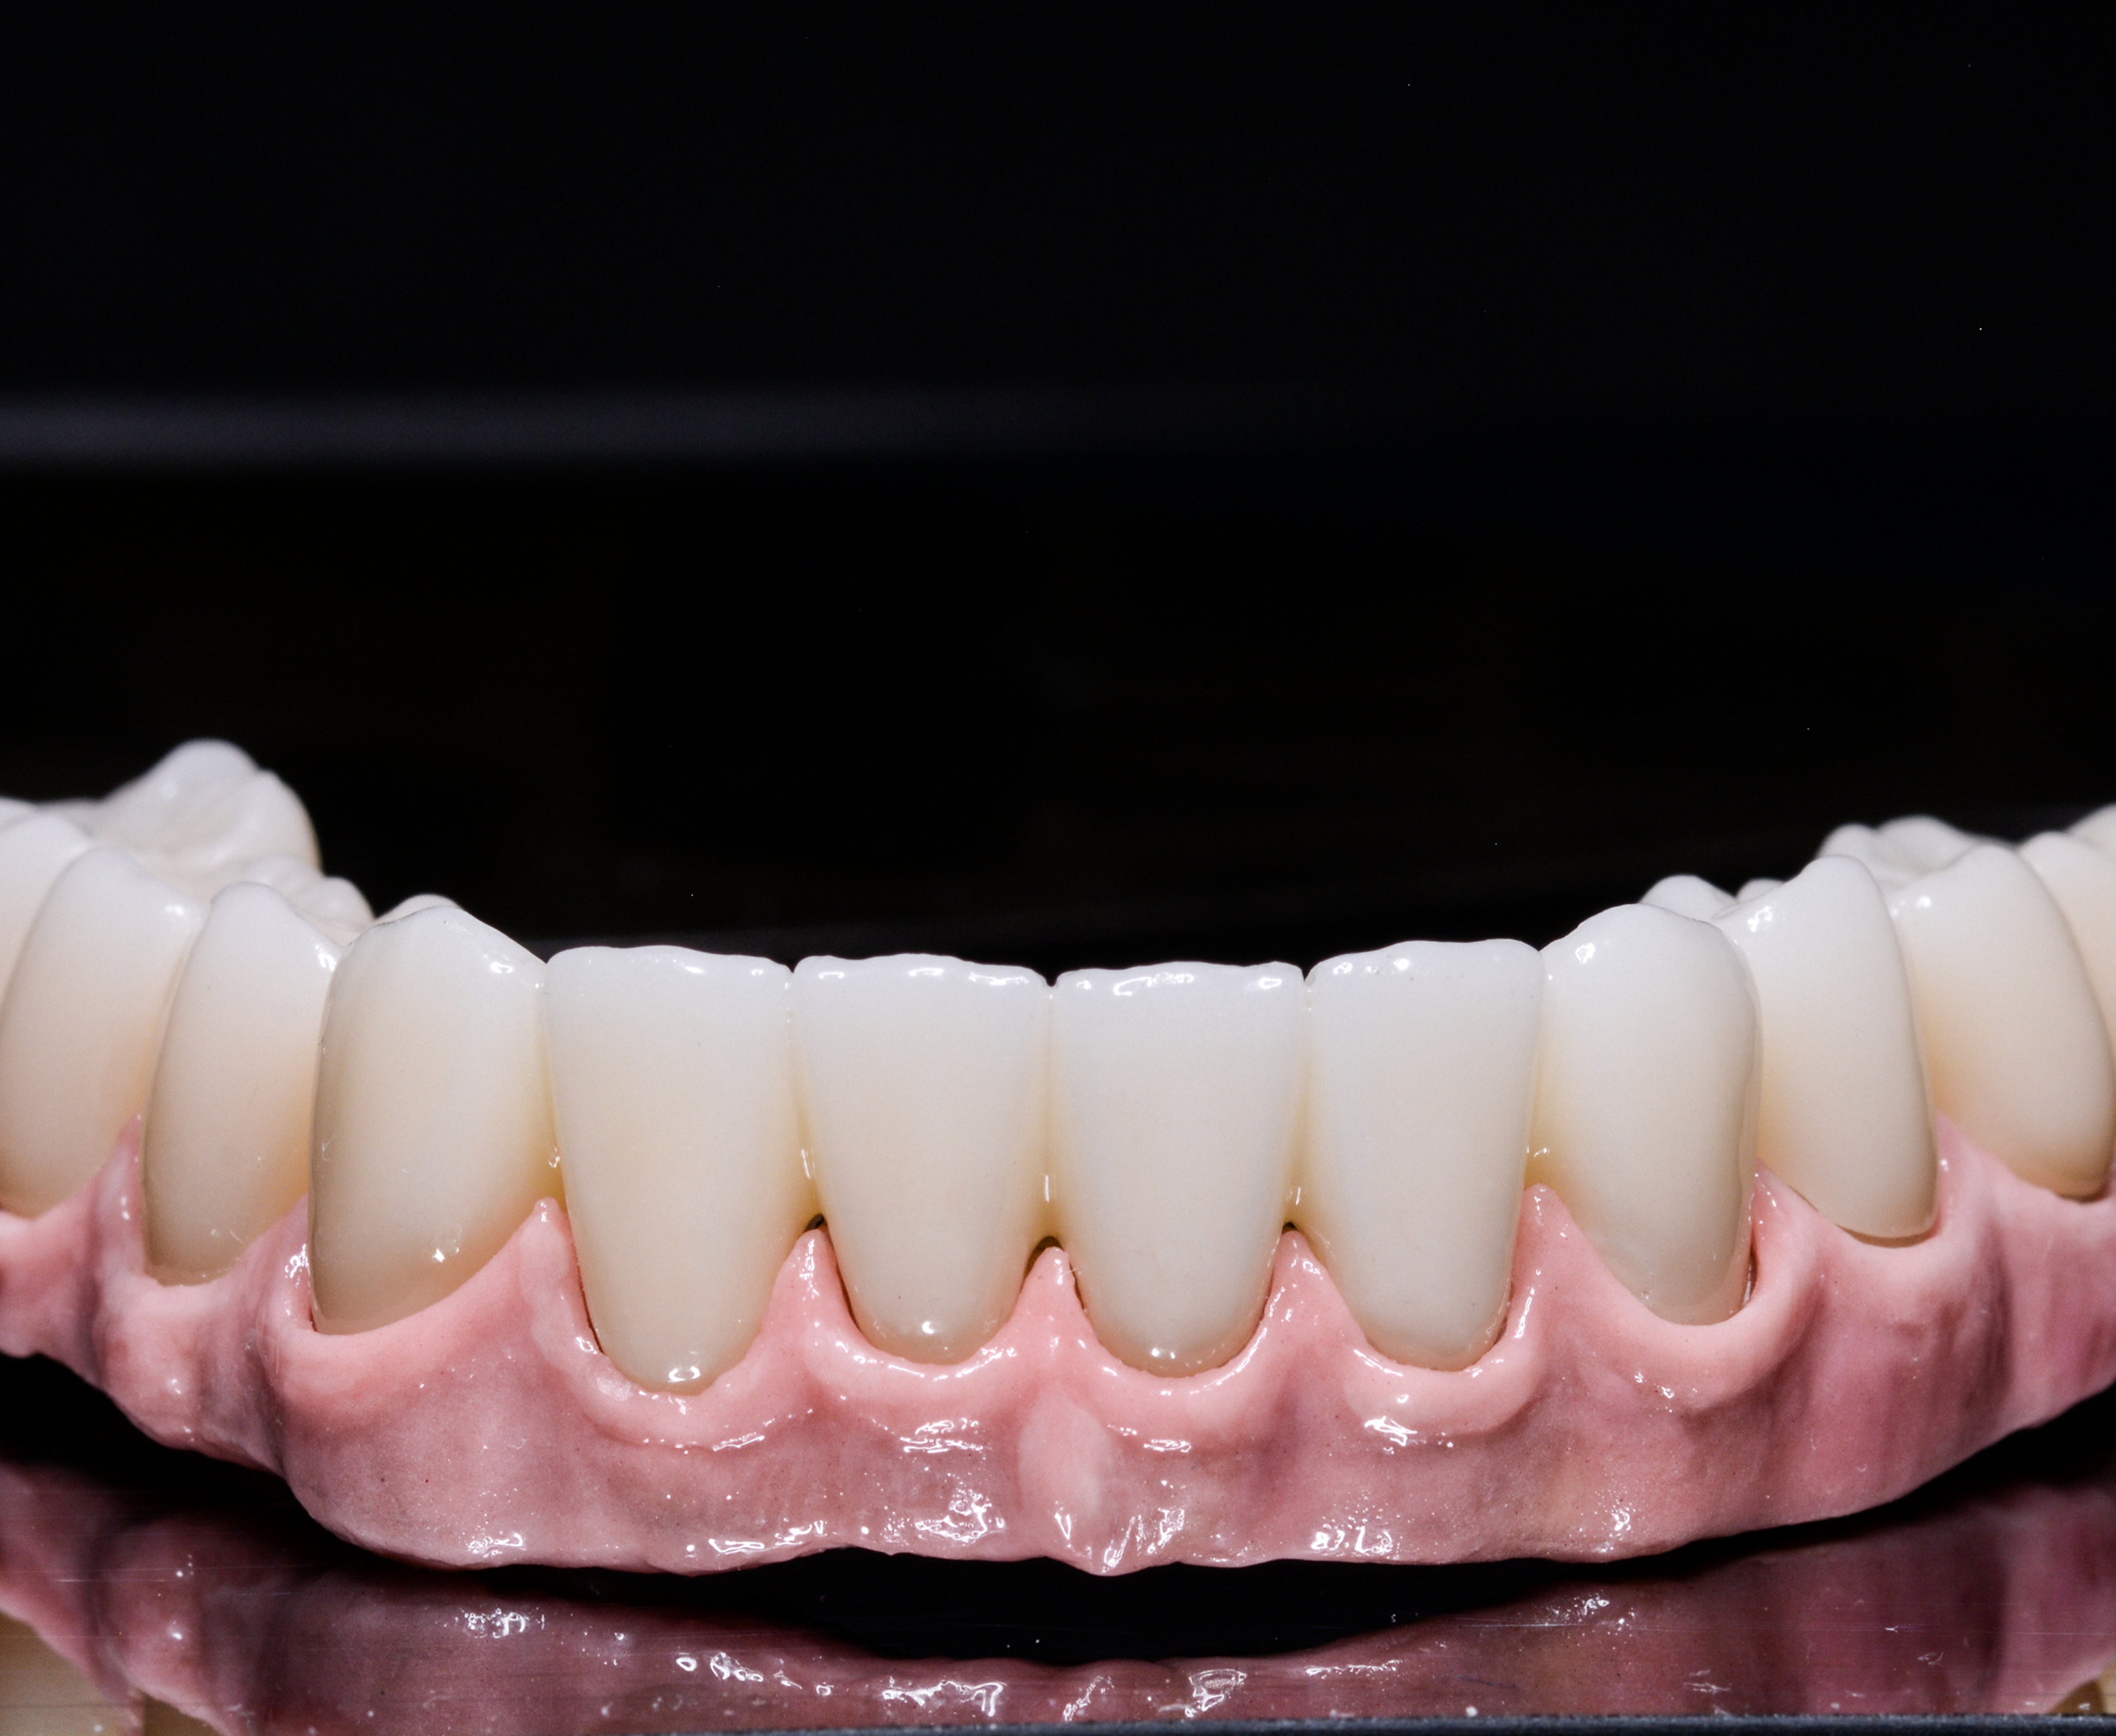

Days 3–4 — Prosthetic Fabrication

- Digital impressions

- Fabrication of his temporary full-arch fixed bridge

- Adjustments for bite, comfort, and natural aesthetics

Day 5 — Final Fitting of Immediate Prosthesis

- Secure placement of temporary full-arch teeth

- Immediate improvement in chewing, speech, and smile appearance